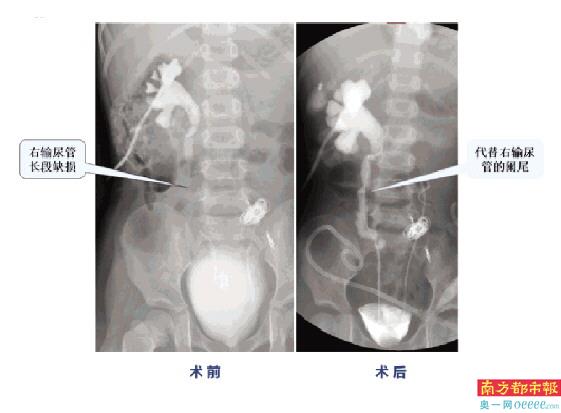

术前术后的对比。

6月9日,手术按计划进行,泌尿外科主任李守林教授亲自主刀。术中,李守林教授团队小心分离了孩子的输尿管,切除狭窄的疤痕后,左侧输尿管吻合成功。然而,右侧输尿管与术前预估一样,缺损长达5cm以上,没办法吻合。原计划将右侧输尿管接到对侧肾盂,由于瘢痕严重无法操作。有着丰富尿路重建经验的李守林教授,注意到患儿阑尾与右输尿管位置靠近,血管蒂够长。于是,将阑尾移植后与残留的右输尿管吻合,代替了缺损的输尿管,解决了右侧输尿管长段缺损的难题。手术顺利完成!

术后,小宇恢复良好。术后第二周检查发现,她的右输尿管顺畅,因此也顺利拔除了右肾造瘘管。从此,她可以自主排尿了,父母脸上也有了久违的笑容。